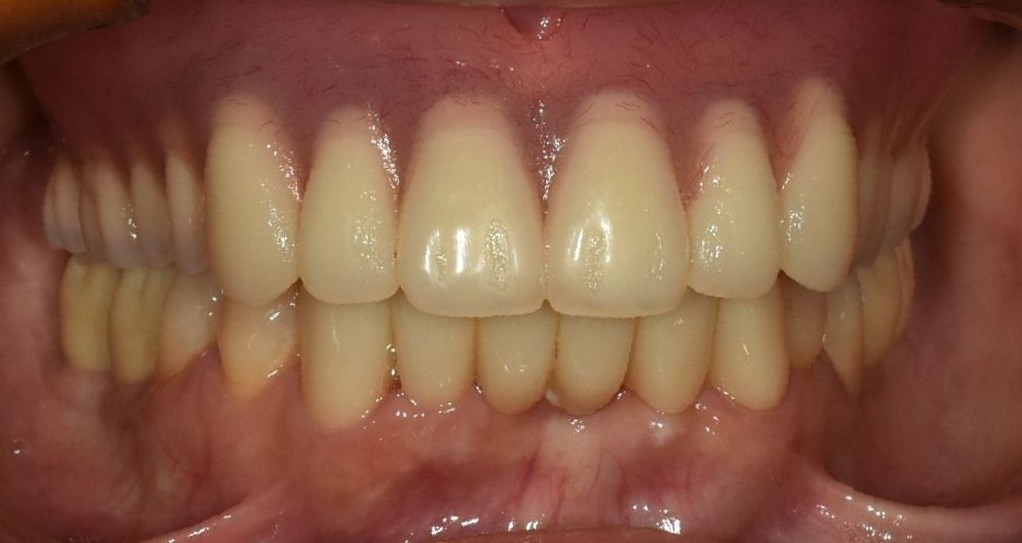

また、治療後の口元の状態が次の画像になります。

とても自然な口元になっています。